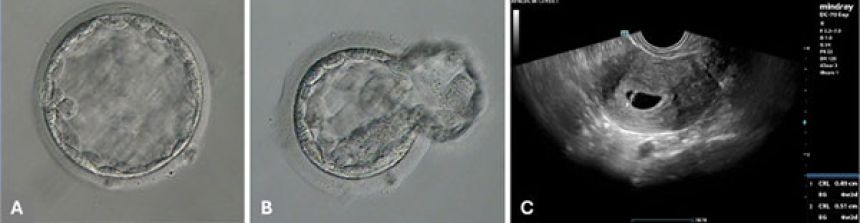

この画像を大きなサイズで見る実験では、5つの卵子に自動ICSIを行い、そのうち4つが正常に受精した。

手作業で行われた3つの卵子もすべて受精したが、自動ICSIで受精した胚のひとつが最も成長し、凍結保存された後、女性の子宮に戻されて妊娠が成立。健康な男の子が無事に生まれた。